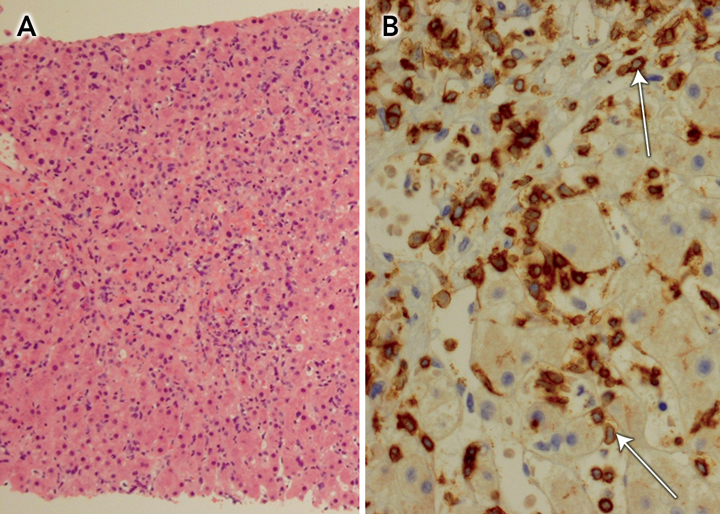

Abdominal computed tomography confirmed gross splenomegaly, with the spleen being 24 cm long on its major axis, but no lymphadenopathy. Microscopic examination of a liver core biopsy specimen revealed an atypical lymphoid infiltrate in the sinusoids, especially around central veins (Box), with immunophenotype bcl-2+, CD3+, CD43+, Ki67+, ALK1 −, bcl-6 − , CD5 −, CD10 −, CD20 −, CD30 −, CD79 − and cyclin D1 − . Subsequent genetic studies of a bone marrow biopsy specimen revealed rearrangement of the T-cell receptor γ-chain gene, consistent with hepatosplenic T-cell lymphoma (HSTCL).